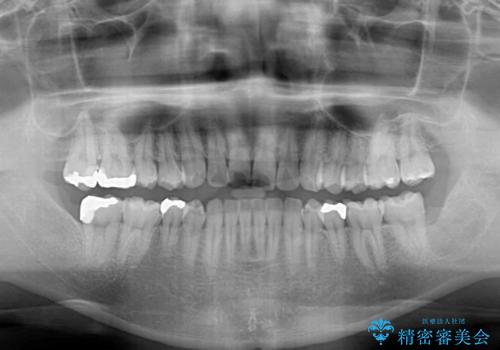

インビザライン・ライトによる矯正治療の後戻り改善

- 矯正治療の後戻りを気にして来院された患者様です。

後戻りは軽微でしたので、インビザライン・ライトにより矯正治療を行うこととしました。

再矯正後の後戻りを防ぐため、歯列排列後に、下顎前歯はワイヤーによる固定を行いました。

下顎前歯の歯列を動かないようにしておくことで、上顎前歯の後戻り防止にも効果を発揮します。